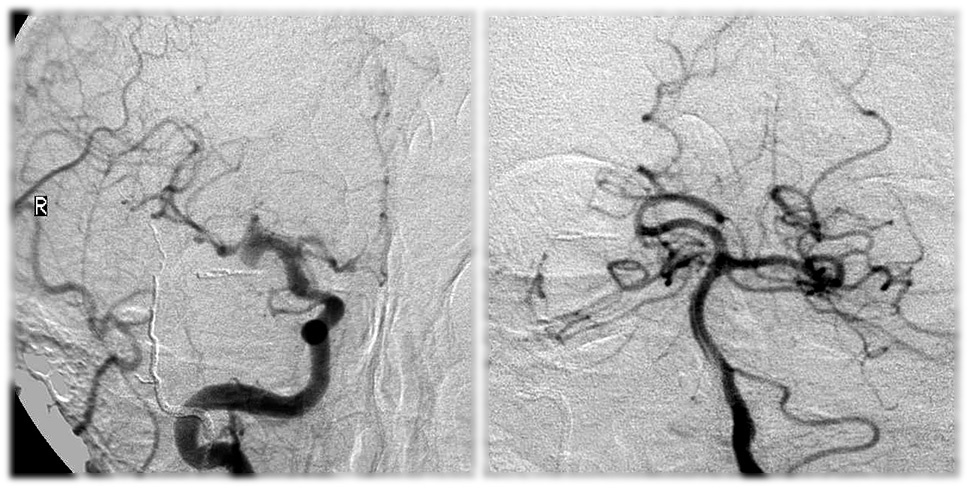

Хирургические процессы при эмболизации гемангиомы на фото

Раздел: Снимки-откровения